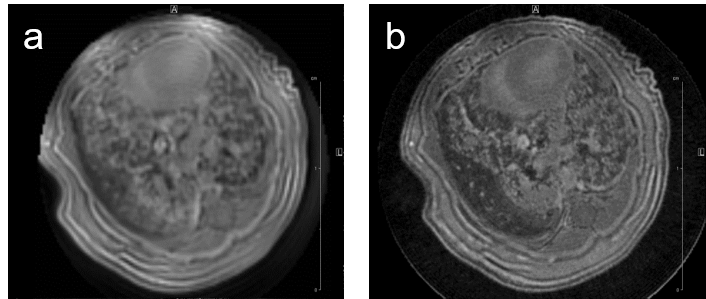

MRI may be used to quantitatively measure lung tumor burden and to follow up e.g. tumor growth. Images of a transgenic mouse model of hyperproliferation in the lung show clearly the replacement of the lung parenchyma Fig. 5.

Fig. 5: Mouse lung MRI. Exemplary axial MR-images of a mouse lung with hyperplasia: (a) respiratory-gated UTE-3D sequence with a repetition time of 8.0 ms, echo time of 20 µs, slice thickness/interslice distance: 0.39/0.39 mm, field of view 2.50x2.70x5.00 cm3 and a matrix of 128/128/128 and (b) respiratory-gated ZTE-3D sequence with a repetition time of 4.0 ms, echo time of 0 µs, slice thickness/interslice distance: 0.16/0.16 mm, field of view 3.00x3.00x4.00cm3 and a matrix of 256/256/256.